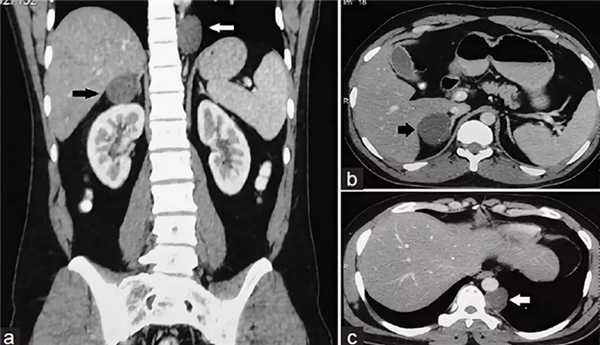

Киста надпочечника — довольно редко встречающееся заболевание надпочечников. Кисты обычно закладываются в эмбриональном периоде, но в течение многих лет постепенно растут и не диагностируются, а выявляются лишь при проведении расширенного ультразвукового обследования органов брюшной полости и КТ. Как правило, кисты надпочечников встречаются в виде одиночных кистозных поражений (чаще одностороннее), довольно редко они наблюдаются как множественные или двухсторонние изменения.

- Киста. О наличии кисты надпочечника свидетельствует анэхогенная округлая область с четкими контурами, плотной гиперэхогенной капсулой, дистальным усилением.

Киста надпочечника

Киста надпочечника (или инциденталома надпочечника) - это случайно выявленное образование надпочечника. Как правило, кисты надпочечника обнаруживают при выполнении пациенту ультразвукового исследования (УЗИ), компьютерной томографии (КТ) или магнитно-резонансной томографии (МРТ), которые проводятся пациенту не по поводу заболевания надпочечников, а по другим причинам.